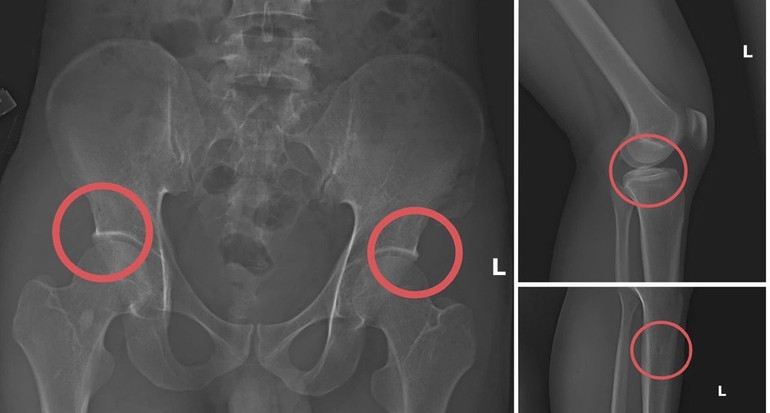

Bản phim chụp XQ một số tổn thương xương do đối tượng tạo ra nhằm trục lợi tiền bảo hiểm nhân thọ.

Theo Công an tỉnh Phú Thọ, đường dây trục lợi bảo hiểm bằng thủ đoạn tự đục vỡ xương khớp nhằm tạo thương tích giả do Tạ Minh Châu (SN 1996), nguyên cán bộ Trung tâm Y tế huyện Cẩm Khê cầm đầu.

Lợi dụng thời gian dài công tác trong ngành và am hiểu cấu trúc xương, khớp, Châu đã xây dựng quy trình trục lợi theo chuỗi khép kín gồm: Vận động người mua bảo hiểm nhân thọ, trực tiếp gây thương tích bằng thuốc mê và các dụng cụ tác động lực, sau đó dựng hiện trường giả để hợp thức hóa hồ sơ điều trị.

Đáng chú ý, Châu trực tiếp thực hiện hành vi tiêm thuốc mê rồi dùng kim tiêm, búa để tác động vào xương người mua bảo hiểm, tạo nên các vết vỡ xương tương tự tai nạn thật. Khi thương tích đã tạo xong, Châu tiếp tục hướng dẫn các đối tượng dựng hiện trường giả như điện giật ngã, trượt chân ngã suối nhằm hợp thức hóa bệnh án và hoàn thiện hồ sơ yêu cầu chi trả.